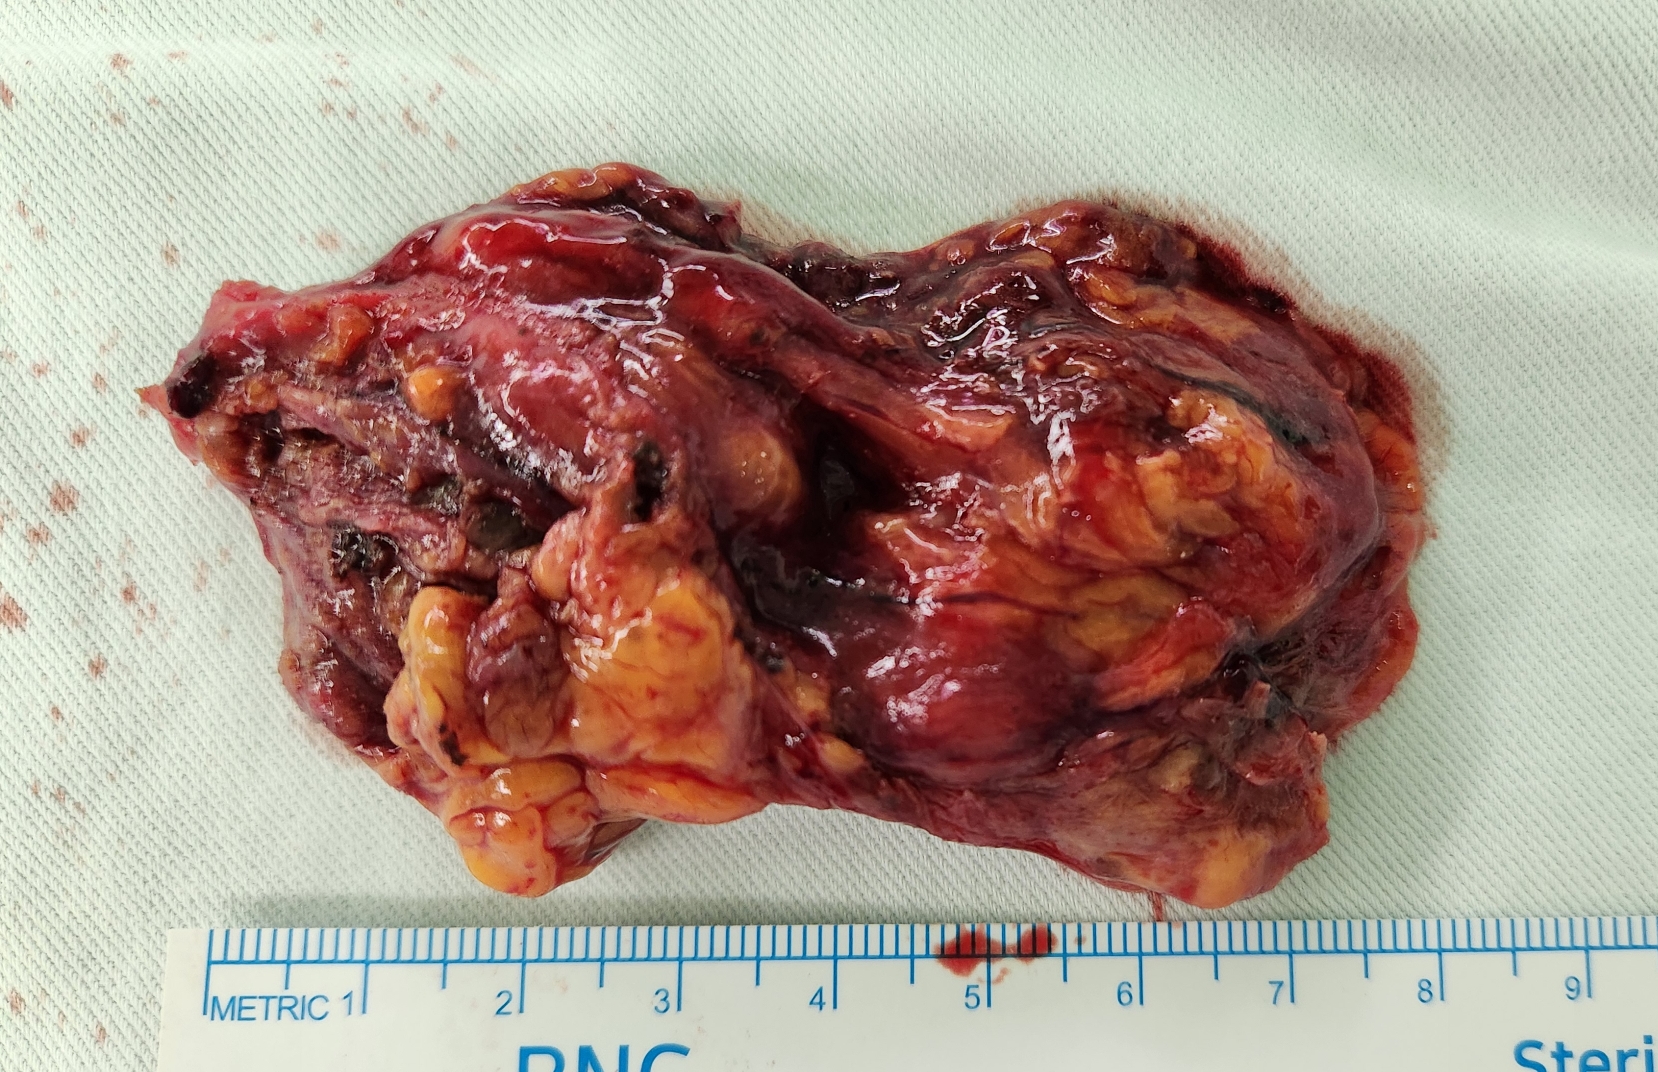

제거한 림프관종입니다.